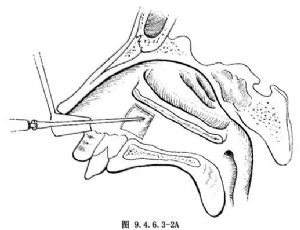

3.開窗 於下鼻道已暴露的骨壁處用上頜竇彎形骨銼穿刺至上頜竇(圖9.4.6.3-2)。